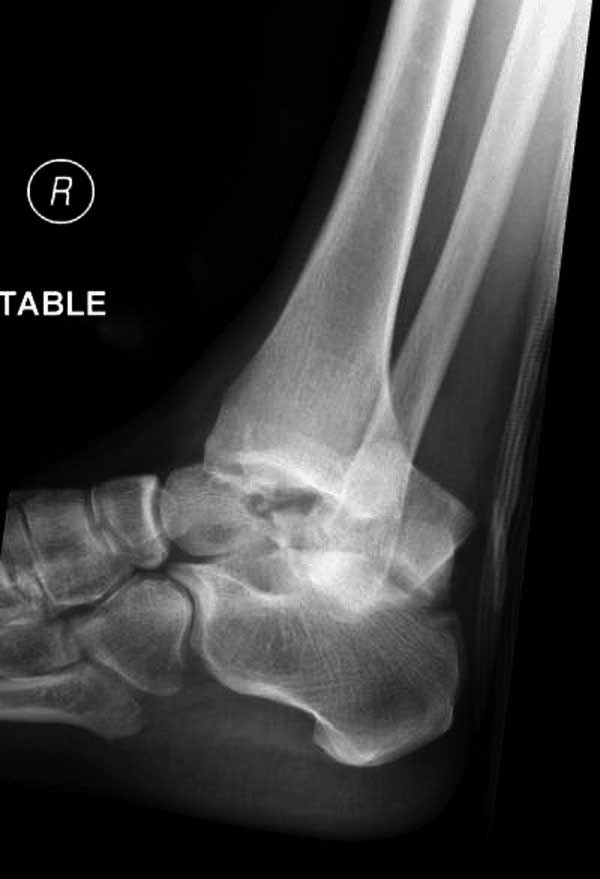

Женщина 28 лет, политравма.

По протоколу обследования больных с травмой сделаны все исследования и выставлен диагноз: разрыв печени и селезенки; множественные переломы ребер и лицевого черепа; стабильный перелом позвоночника, переломо-вывих головки левого бедра, перелом диафиза правого бедра, переломо-вывих правого тарана.